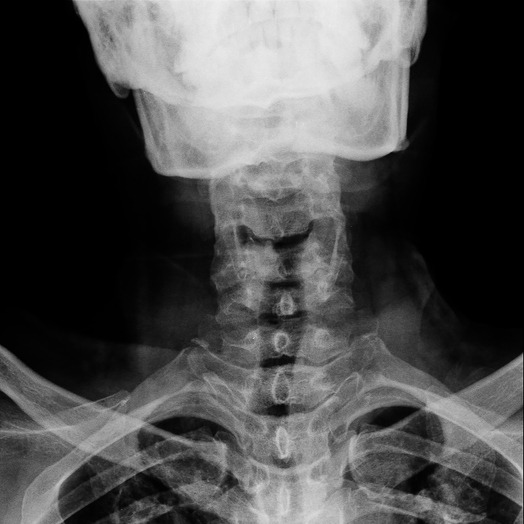

Spondilosi cervicale

La spondilosi cervicale è una condizione degenerativa che interessa le vertebre e i dischi della colonna vertebrale nel tratto cervicale.

Solitamente, pertanto, la diagnosi viene confermata sulla base di alcuni esami strumentali che consentono di valutare visivamente i danni a carico della colonna vertebrale, come:

• radiografie: possono mostrare riduzioni dello spazio tra le vertebre, osteofiti e altre modifiche alla struttura delle vertebre;